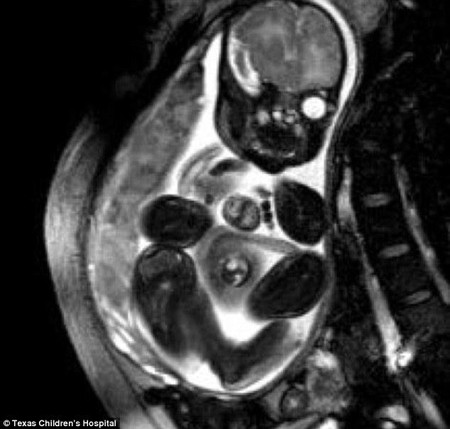

美女婴心脏长体外手术后平安出院(6)

据英国《每日邮报》1月24日报道,美国德克萨斯州一名出生时先天心脏便长在体外的女婴,在接受手术后,已于当地时间23日出院回家。据悉,经过手术,这颗小心脏已安全地回到她的胸腔内。